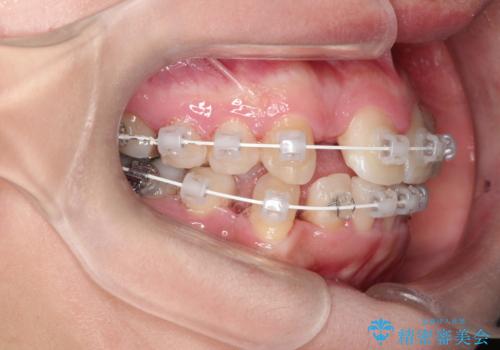

- 審美装置

残った乳歯と上下左右の永久歯を1本ずつ抜歯して、ワイヤーにて矯正することとしました。